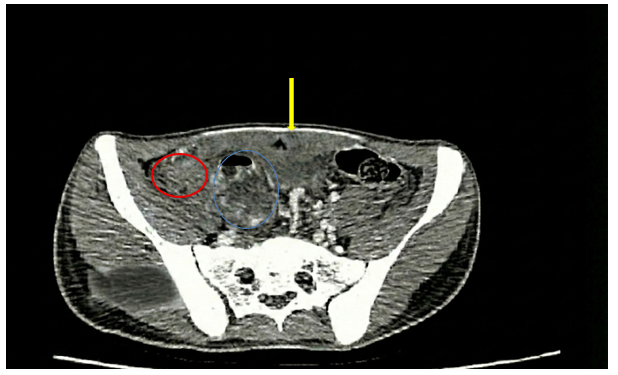

- CLVT ổ bụng (29/11/2025):

Hình ảnh ổ dịch – khí vùng tiểu khung kích thước 22x15mm (vùng khoanh tròn màu xanh dương), thâm nhiễm mỡ rộng (vùng khoanh tròn màu đỏ), dày phúc mạc kèm dịch vùng tiểu khung dày 12mm (vùng mũi tên màu vàng)